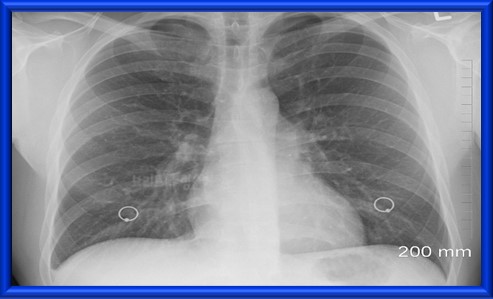

- 흉부 X선 검사: 흉부 X선 검사는 기도 또는 폐의 다른 문제를 확인하기 위해 실시한다.